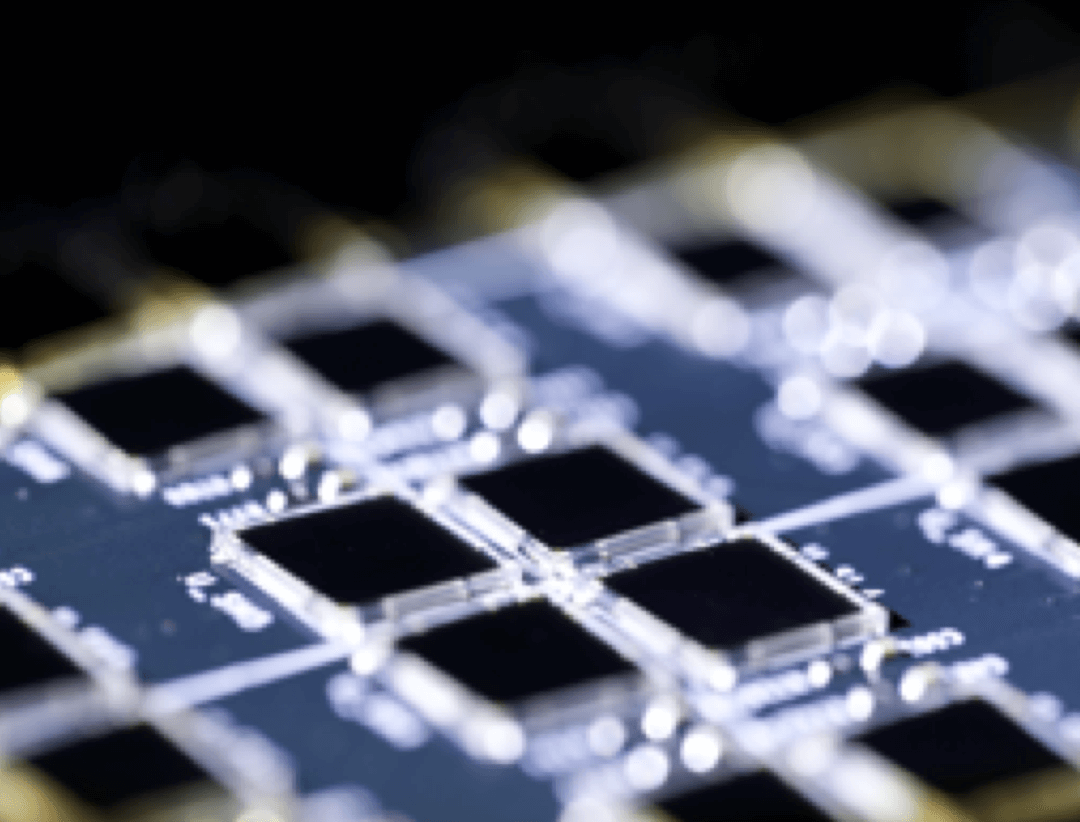

600 x 600

超大矩阵,高精度超清重建